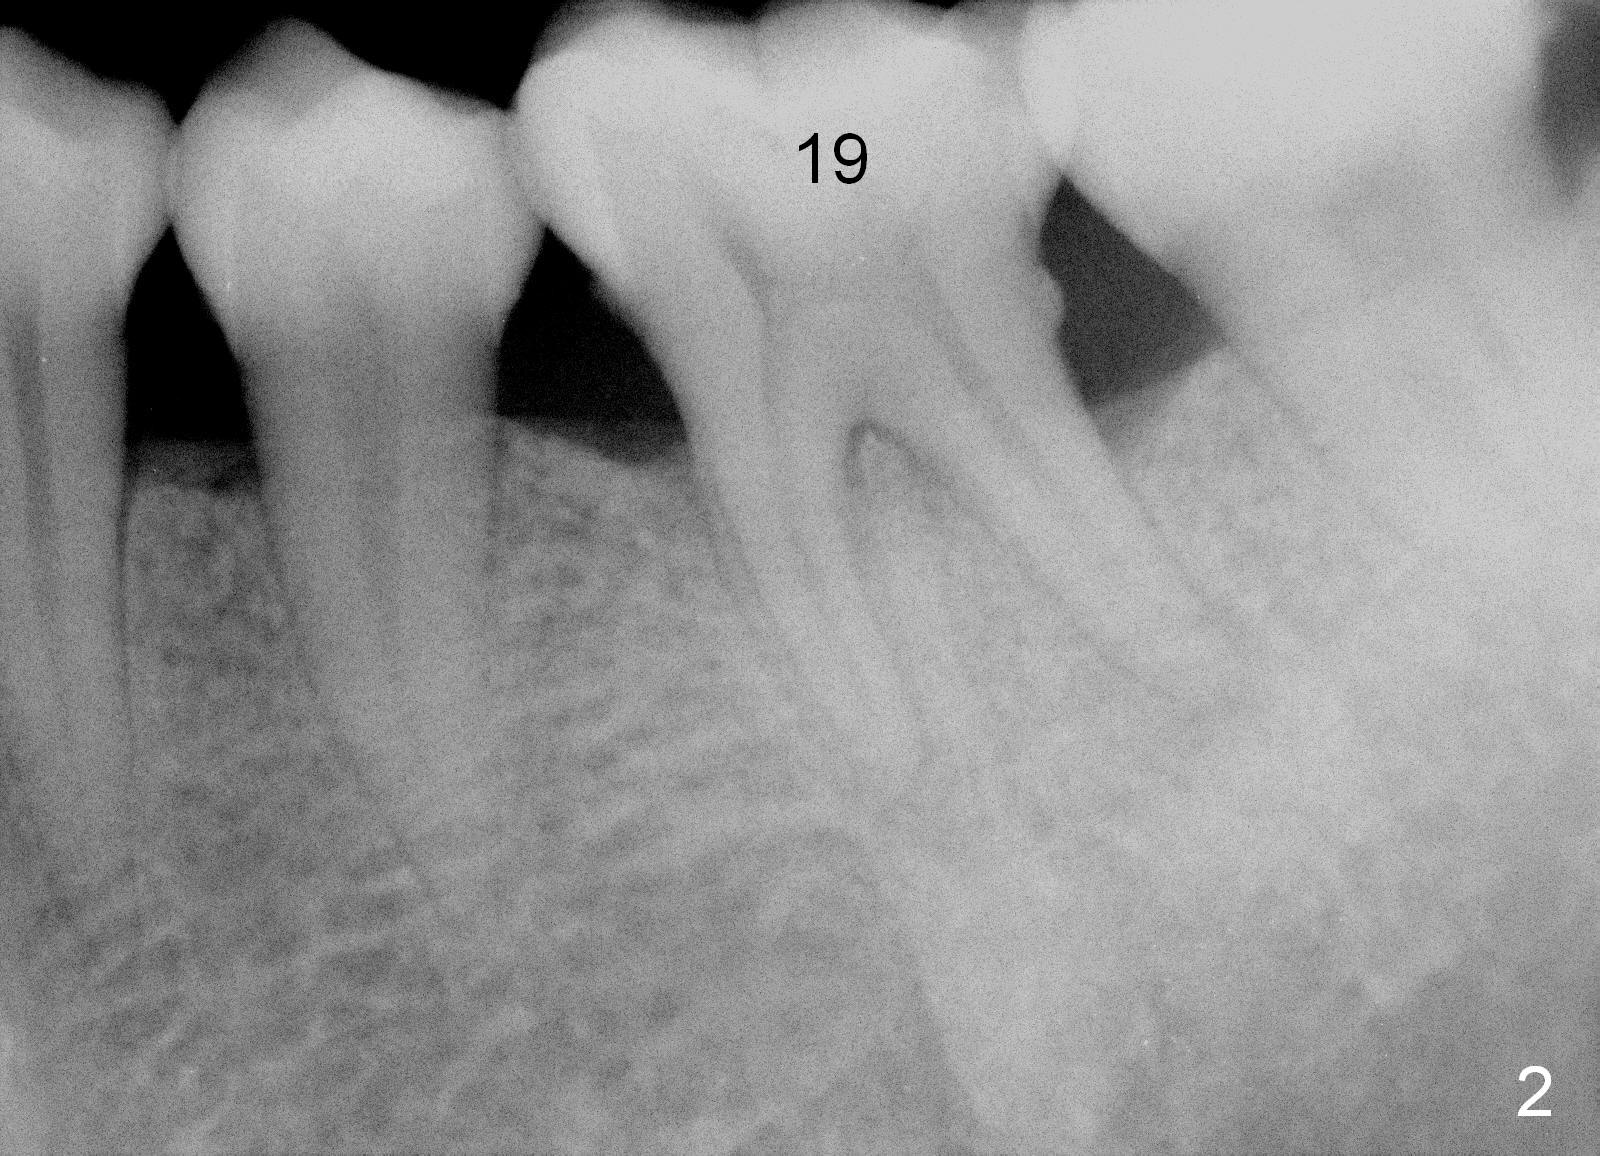

A 43-year-old lady has generalized moderate localized advanced chronic periodontits (Fig.1,2). In spite of 4 quadrant scaling & root planing, the tooth #19 develops 2 perio abscesses (Fig.4 with insertion of 2 guttae perchae); periodontal ligament spaces increases (compare Fig.2,4). It appears that the tooth is non salvageable and should be replaced with an immediate implant (Fig.5). The extraction socket will be treated with Metronidazole. A 2 mm pilot drill is used to start osteotomy in the septum (14 mm deep), followed by reamers until 3.5 mm. A 5x17 mm tap is placed to test stability. If the stability is high, place a 5.3x12 mm SM implant. If insertion torque is too high, use the corresponding drill before re-place the implant. Collagen dressing is placed in the peripheral and deep portion of the sockets, while bone graft in the top portion of the sockets (near implant threads). Use 1 or 2 amalgam carriers to deliver the graft lateral to the implant precisely so that a cover screw does not have to be placed. Next place a cemented abutment. If trajectory of the implant is correct, an abutment as large as 7.8x5(3) mm could be used (pink). Fabricate an immediate provisional. Do not over trim the margin of the provisional so that it can cover the socket completely.